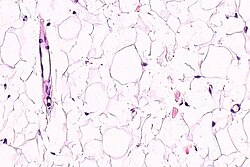

- The layer below the skin is the subdermis (AKA hypodermis, AKA subcutaneous tissue).

- It is below the dermis and consists of adipose tissue.[3]